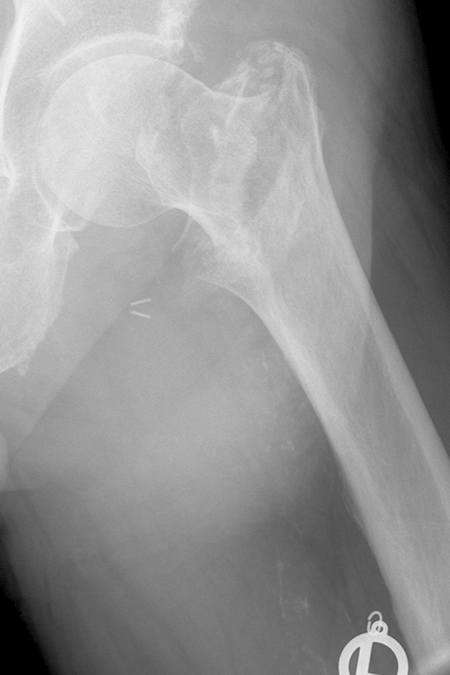

PERTROCHANTÄRE OBERSCHENKELFRAKTUR

Bild Frakturverlauf pertrochantaere Fraktur Modell

Die Faktur verläuft zwischen dem Großen Rollhügel (trochanter major) mit den Ansätzen des gluteus medius und minimus (Streckung und Abspreizung der Hüfte) und dem Kleinen Rollhügel (trochanter minor), an dem der Ileopsoas (Hüftbeugung) ansetzt. Die Patient*innen können nach dem Sturz mit starken Schmerzen in der Hüftregion in den meisten Fällen nicht mehr stehen oder gehen.

Pertrochantaere Fraktur vor der Operation